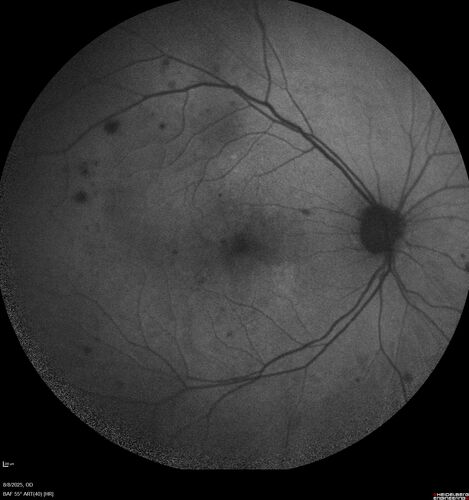

NPDR and Severe macular ischemia sudden vision loss

60 year old female with sudden vision loss OD 1 week ago. VA 20/63, 20/200. OCT-A and FA shows severe macular ischemia OU